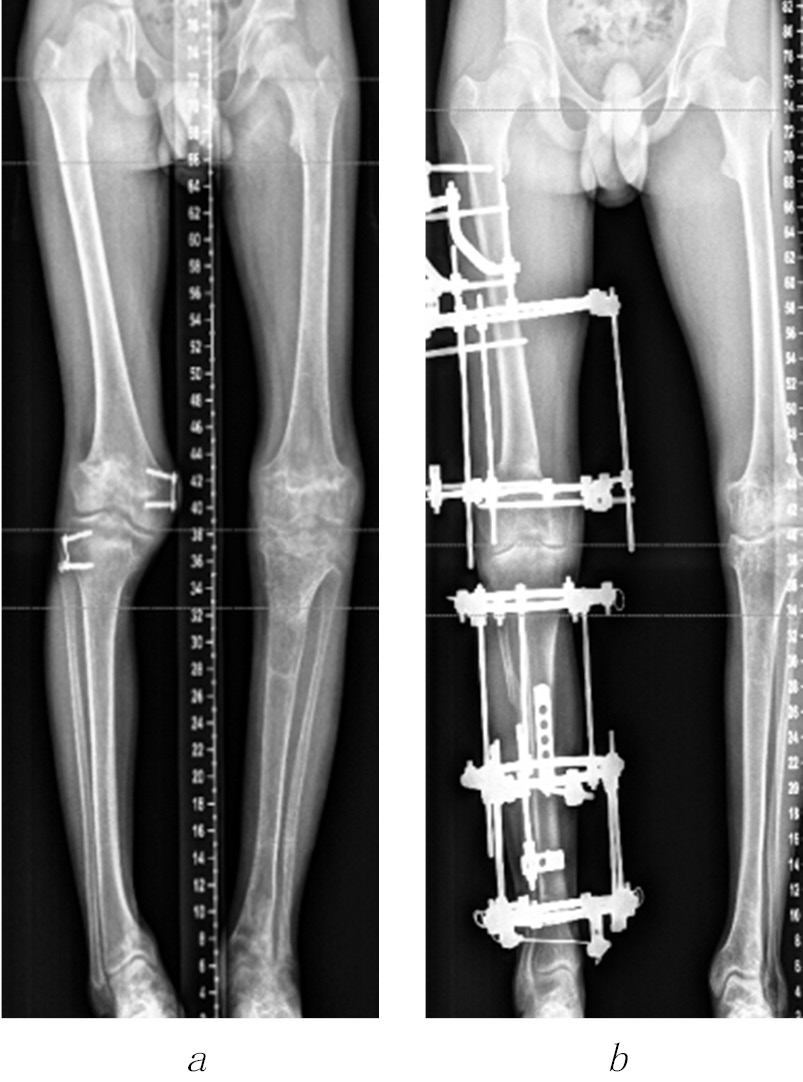

The shortening of the lower limb by 4 cm or more, the shoulder by 6 cm or more, and the forearm by 5 cm or more were considered an indication for surgical treatment, taking into account the age of the child. In the presence of angular deformities of the limb segments, accompanied by a shortening of 3 cm or more, one-stage correction of the length and shape of the limb segment by osteotomy was performed using compression-distraction osteosynthesis. At the final stage of treatment, to correct the multiplanar deformities of the bone metaphyses forming the knee and ankle joints, the Ortho-SUV reposition unit was used in three patients, which allowed to reduce the time and improve the quality of reposition (Fig. 1).

Fig. 1. Radiographs of patient G.’s lower extremities before (a) and during the correction of the shape and length of the right and left lower extremities using the Ortho-SUV reposition unit (b) and the standard layout of the Ilizarov apparatus (c)